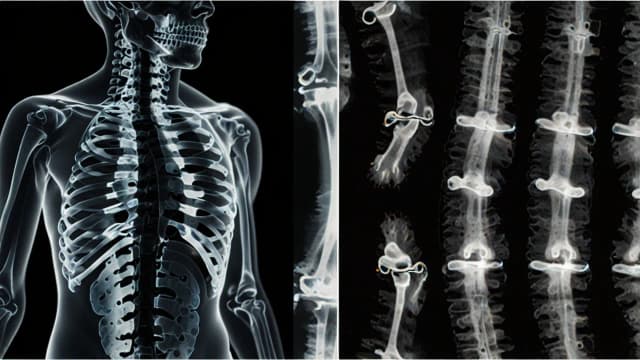

Leczenie przepukliny jądra miażdżystego: metody, które przynoszą ulgę

Poznaj skuteczne metody leczenia przepukliny jądra miażdżystego. Od terapii zachowawczej po operację kręgosłupa - dowiedz się, jak złagodzić ból i wrócić do zdrowia. Sprawdzone sposoby na ulgę.